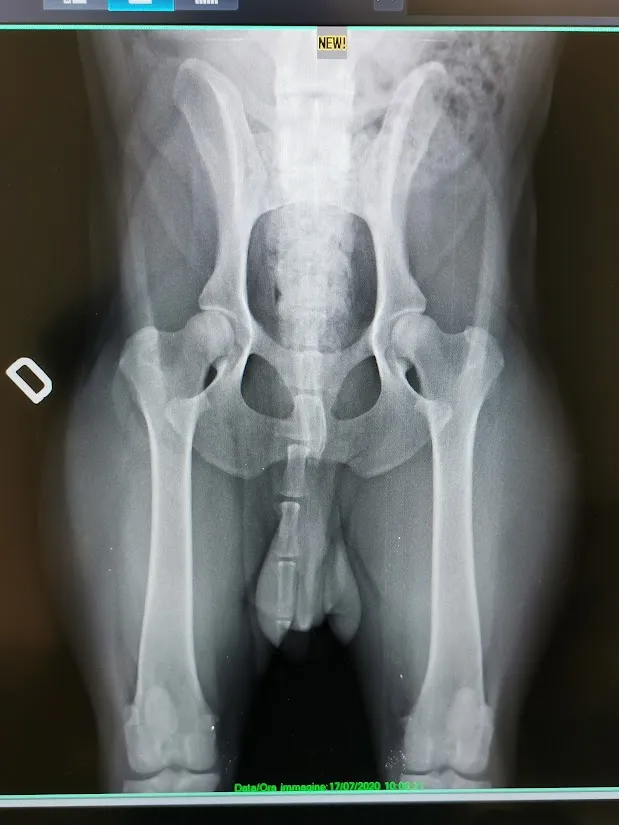

Diagnostica avanzata

Ecografie, radiologie digitali ed esami di laboratorio

Ortopedia e traumatologia

Cura delle lesioni e delle problematiche articolari